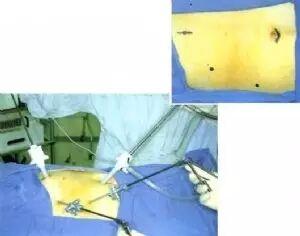

第4步

然后将腹腔镜放入,在腹腔镜的监视下进行各点的穿刺。一般在剑突下2cm穿刺放入10mm套管以备放电凝钩、施夹器等器械;在右锁骨中线肋缘下2cm或腹直肌外缘和腋前线肋缘下2cm各用5mm的套管针穿刺以放入冲洗器和胆囊固定抓钳。